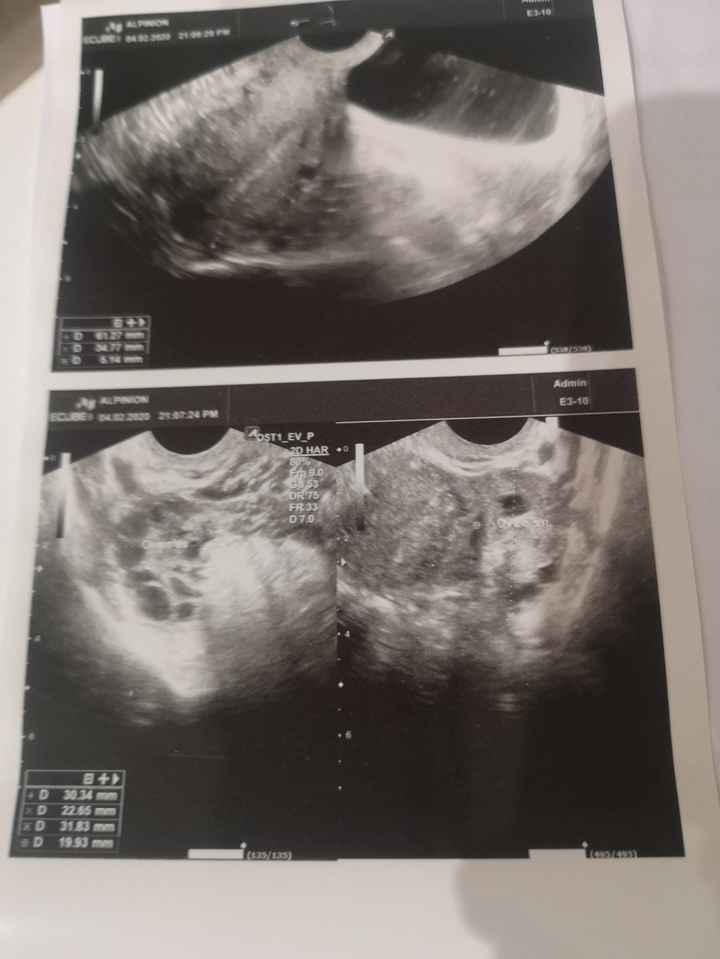

Vi allego una foto del mio referto ginecologico 🙂Test ovulazione e ovaie multifollicolari 2

Test ovulazione e ovaie multifollicolari 3